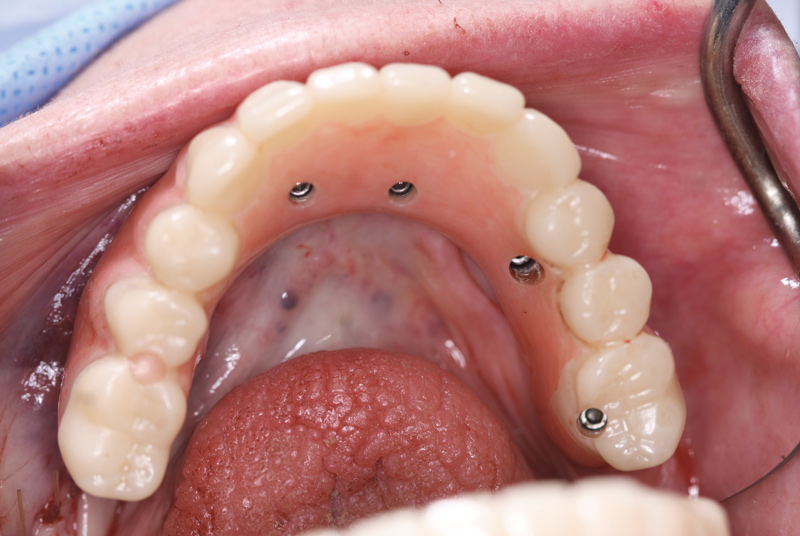

Fig 18. The overdenture was then seated and secured using the original fixation screws.

Figure 18